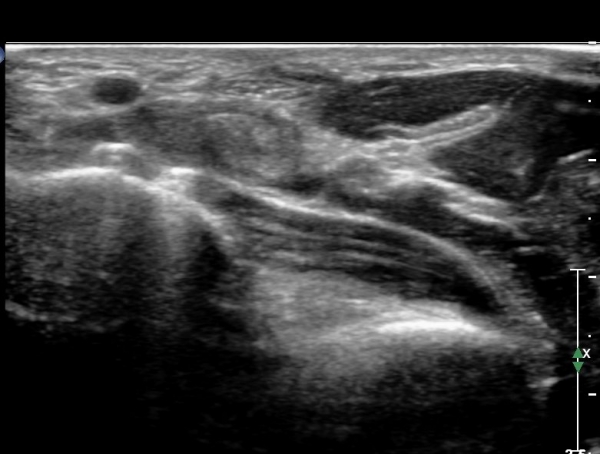

¾Æ·§ÆÈ ÇϺκΠȾ´Ü¸é°Ë»ç¿¡¼­ Àü°ñ°£ ½Å°æ Áö¹è¸¦ ¹Þ´Â  PQ ¿¡¼­ ½Å°æ¸¶ºñ ¼Ò°ß(°í¿¡ÄÚ ±ÙÀ§Ãà)À»

º¸ÀÌÁö ¾ÊÀ¸³ª  FPL ÈûÁÙÀÇ Àú¿¡ÄÚ ºÎÁ¾ÀÌ °üÂûµÇ°í(»çÁø 2, 3) ³»°íÁ¤¹°ÀÌ FPL °ú Á¢ÃËÇϰí ÀÖÀ½ÀÌ °üÂûµÊ(»çÁø 3)